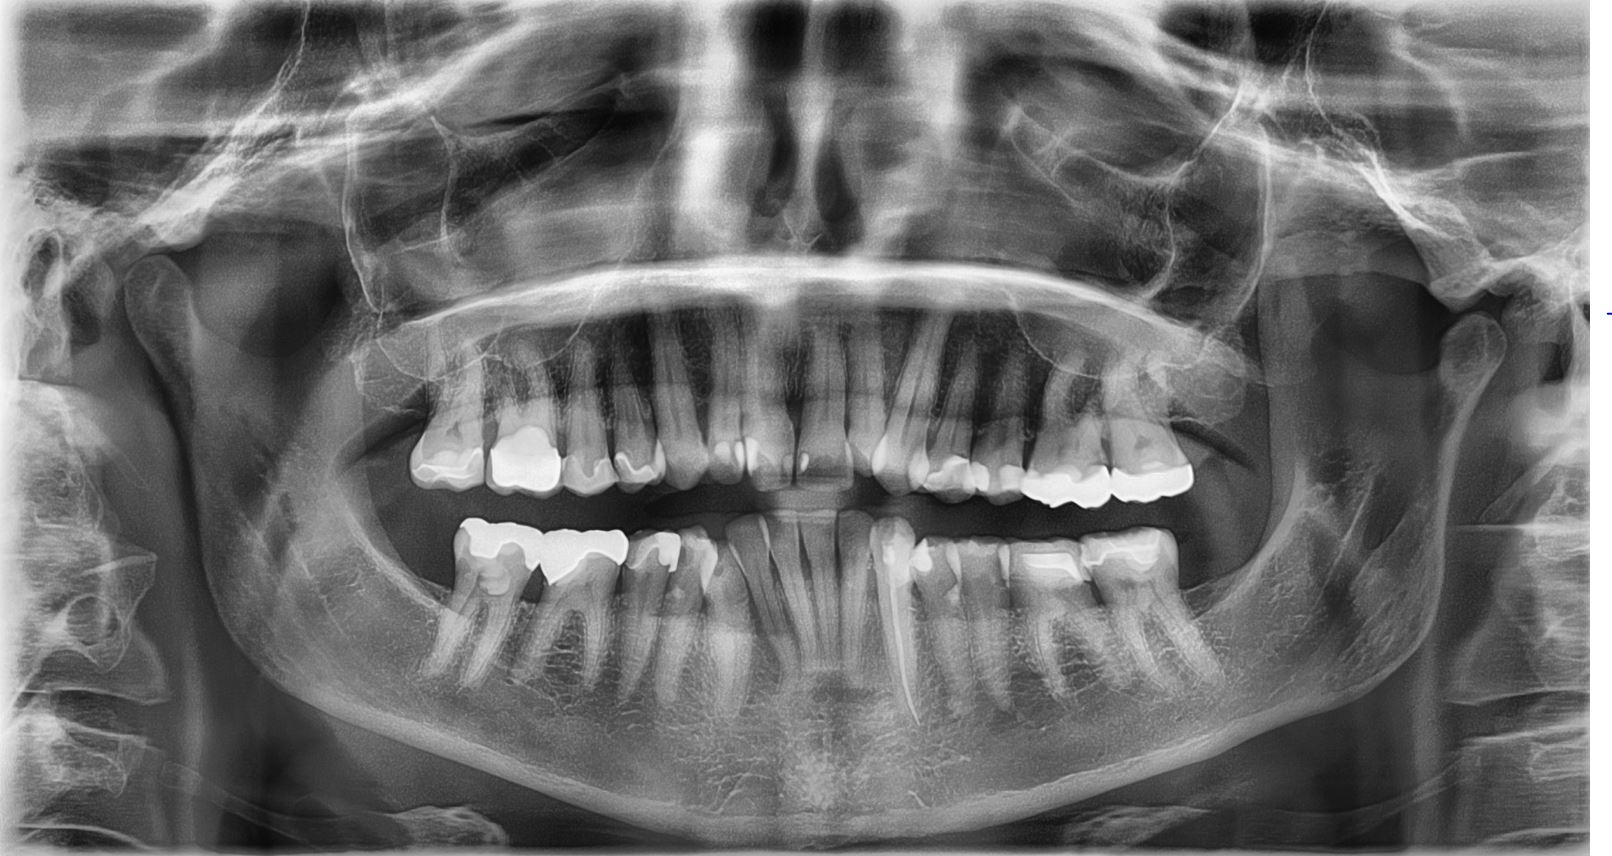

Orthopantomogram (OPG) phantom showing full mandible and maxilla with all teeth, TMJ, sinuses, and surrounding anatomy